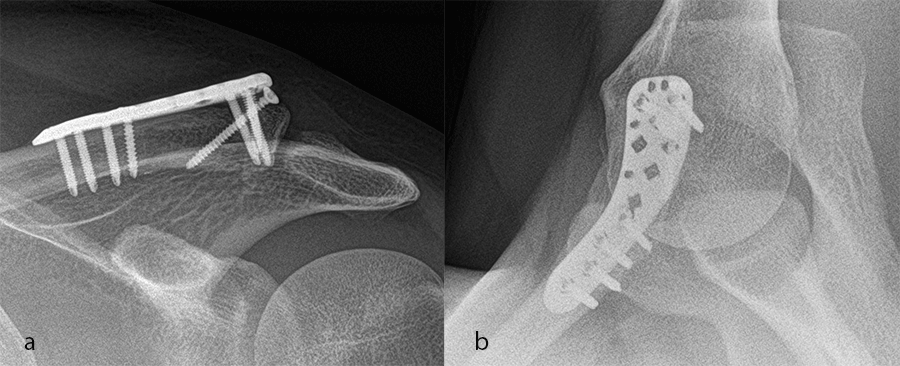

Case 1: lateral plate

A 30-year-old man sustained a lateral fracture to his left clavicle following a fall from his bike (Fig 9). Intraoperative images indicate plate placement and screw insertion (Fig 10). Intraoperative image revealing usage of sutures through the plate for soft- tissue fixation (Fig 11). Image shows the fracture healing at 8 weeks' follow-up (Fig 12).